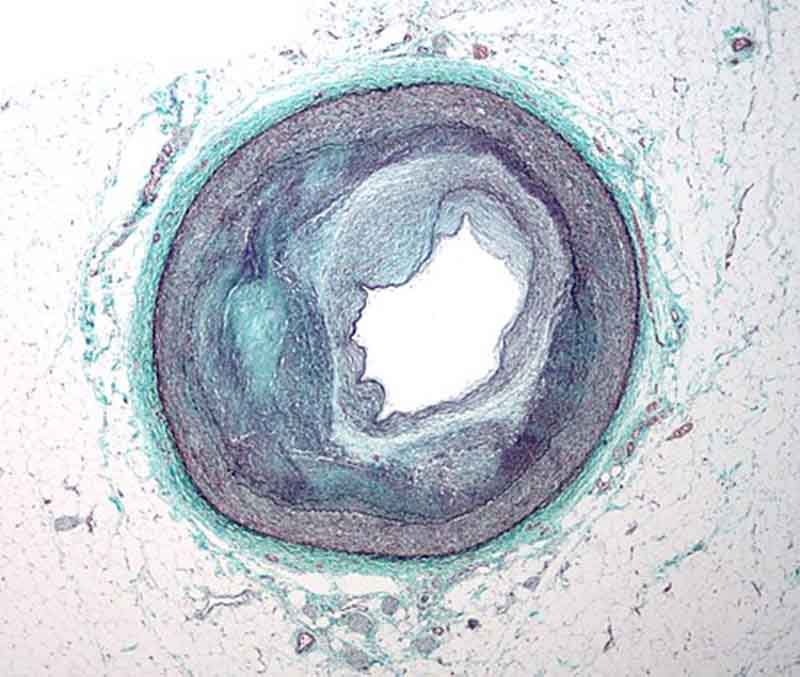

Xơ vữa động mạch (tiếng Anh là atherosclerosis) là sự tích tụ của chất béo, cholesterol, canxi và các chất khác trong, trên thành động mạch. Sự tích tụ này được gọi là mảng xơ vữa. Mảng xơ vữa có thể làm hẹp động mạch, cản trở lưu lượng máu. Mảng xơ vữa cũng có thể vỡ ra, dẫn đến hình thành cục máu đông.

Xơ vữa động mạch là một quá trình phức tạp, bắt đầu từ thời thơ ấu và tiến triển theo độ tuổi. Hiện không rõ chính xác xơ vữa động mạch bắt đầu như thế nào hoặc nguyên nhân gây ra bệnh. Tuy nhiên, sự tích tụ dần dần của mảng bám hoặc dày lên do viêm xảy ra ở bên trong thành động mạch dẫn đến hẹp lòng mạch, làm giảm lưu lượng máu, nguồn cung cấp oxy đến các cơ quan trọng yếu của cơ thể và các chi. (3)